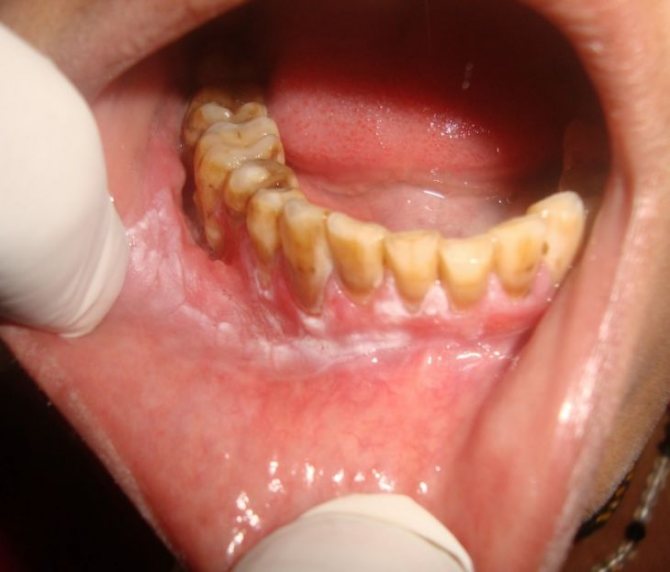

Фото лейкоплакии

Участок поврежденных поверхностей выглядит как гиперкератозная пятнистость – нестандартного разрастания внешних слоев, визуально определяющиеся как измененный эпителий мутного цвета, с четким разграничением.

Место воспаления напоминает ожоговые поражения слизистой оболочки (при неверном пользовании ляписным карандашом) или тонкую бумагу. Попытки соскоблить нестандартные слои остаются безрезультатными – налет крепко держится на месте.

Уровень повреждения тканей может быть разной интенсивности, на его фоне цветовая окраска пятен от сероватого до молочно-белого оттенка. Участки, затронутые аномальным процессом, шероховатые и сухие. При пальпаторном исследовании уплотнения не обнаруживаются, внешних признаков воспаления не существует.

Симптоматическим проявлением болезни служит разрастающееся ороговение, вызывающее значительное увеличение и утолщение верхних слоев слизистых покровов. Участки веррукозного поражения находятся выше рядом расположенных тканей, отличаются резким цветовым оттенком. Пальпаторное исследование подтверждает наличие поверхностного уплотнения.

- бородавчатый – визуально определяется как бугристые образования серовато-беловатого окраса, с плотной консистенцией и размерами до 3 мм в высоту.